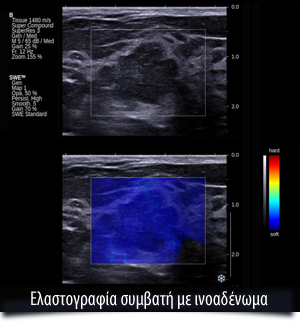

Η πλέον σύγχρονη τεχνική είναι η Shear Waves, με την οποία η εικόνα αποκτά μια νέα δυναμική και απαλλάσσει τον ασθενή αλλά και τον ακτινολόγο από την πίεση της κεφαλής των υπερήχων. Με τη νέα μέθοδο η κεφαλή, αφού απλά σταθεροποιηθεί πάνω από τη βλάβη, στέλνει ήχους, οι οποίοι επιστρέφουν δημιουργώντας ένα κύμα παραμόρφωσης στη βλάβη, το οποίο και αναλύεται από την ίδια την κεφαλή. Η μέθοδος αυτή έχει δύο πολύ σημαντικά πλεονεκτήματα. Εκτός του ότι είναι και ποσοτική και όχι ποιοτική, είναι και αντικειμενική, διότι δεν εξαρτάται από τον χειριστή του μηχανήματος και τον βαθμό πίεσης που θα εξασκήσει, αλλά από την αυτόματη μέτρηση της κεφαλής.

Η μέτρηση γίνεται σε Kilopascal και το όριο είναι 72 kilopascal. Πάνω από αυτό το όριο, η βλάβη χαρακτηρίζεται ως κακοήθης.